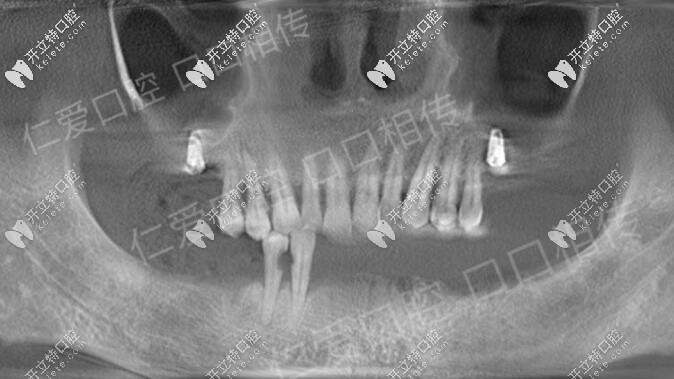

諾貝爾ALL-ON-6即刻負(fù)重種植牙馬上有牙,武漢人都來這種牙

諾貝爾即刻種植即刻負(fù)重種植牙,無牙頜顧客的福音,ALL-ON-6即刻負(fù)重,植入6顆種植體就可種出整排牙。